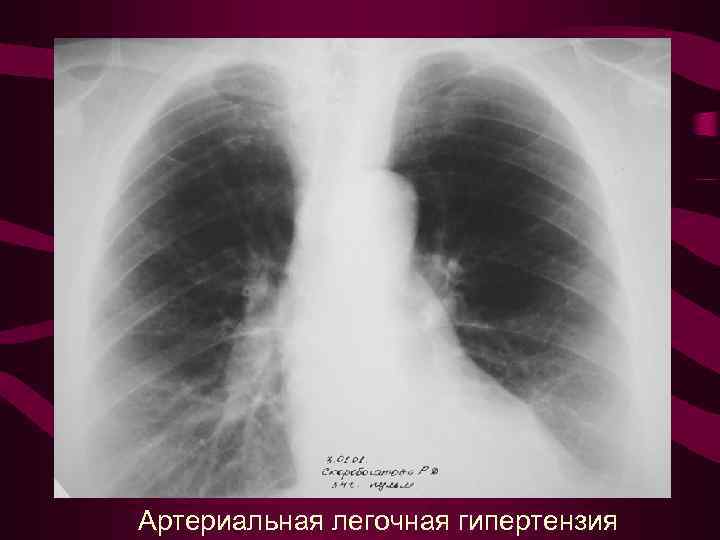

Артериальная легочная гипертензия

Артериальная легочная гипертензия

Диаметр левой легочной артерии в норме 23 - 25 мм Поперечник нисходящей ветви правой легочной артерии 15 -17 мм Расширение левой легочной артерии и нисходящей ветви правой легочной артерии являются объективными признаками артериальной легочной гипертензии

Диаметр левой легочной артерии в норме 23 - 25 мм Поперечник нисходящей ветви правой легочной артерии 15 -17 мм Расширение левой легочной артерии и нисходящей ветви правой легочной артерии являются объективными признаками артериальной легочной гипертензии